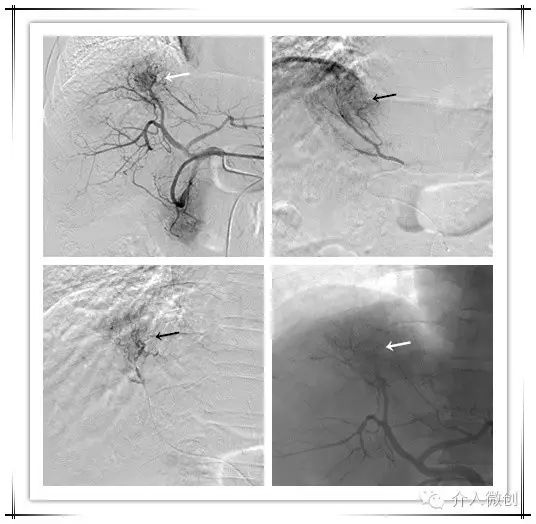

近期出现食管胃静脉曲张破裂出血,予以行TIPS分流减低门静脉压力,联合放射性条植入至门静脉内行癌栓近距离照射治疗,到达标本兼治。

穿刺门静脉造影显示粗大胃冠状静脉

栓堵粗大的胃冠状静脉

TIPS术+放射性粒子条植入治疗